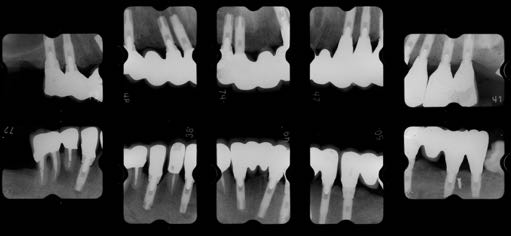

治療前